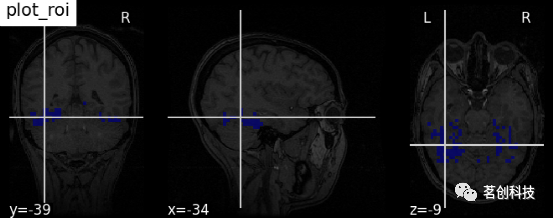

plot_roi:用可选的背景绘制ROI或掩膜。如将haxby数据集上的腹侧颞区图像可视化,并将坐标自动定位于感兴趣区域(roi)。

plotting.plot_roi(haxby_mask_filename, bg_img=haxby_anat_filename,

title="plot_roi")

display.add_contours(img, levels=[.5], colors=' r '):添加轮廓线。

display = plotting.plot_anat(mean_haxby_img, title="add_contours",

cut_coords=[-34, -39, -9])

display.add_contours(haxby_mask_filename, levels=[0.5], colors='r')

display.add_contours(img, filled=True, alpha=0.7, levels=[0.5], colors=' b '):轮廓填充。

display = plotting.plot_anat(mean_haxby_img,

title="add_contours with filled=True",

cut_coords=[-34, -39, -9])

display.add_contours(haxby_mask_filename, filled=True, alpha=0.7,

levels=[0.5], colors='b')

display.add_markers(coords, marker_color=' y ', marker_size=100):添加标记。

display = plotting.plot_anat(mean_haxby_img, title="add_markers",

cut_coords=[-34, -39, -9])

coords = [(-34, -39, -9)]

display.add_markers(coords, marker_color='y', marker_size=100)

display.annotate(scalebar=True):添加比例尺。

display = plotting.plot_anat(mean_haxby_img,

title="adding a scale bar",

cut_coords=[-34, -39, -9])

display.annotate(scalebar=True)

# 进一步的设置可以通过scale_*关键字参数来实现。例如,将单位更改为mm,或者使用不同的比列尺大小

display = plotting.plot_anat(mean_haxby_img,

title="adding a scale bar",

cut_coords=[-34, -39, -9])

display.annotate(scalebar=True, scale_size=25, scale_units='mm')